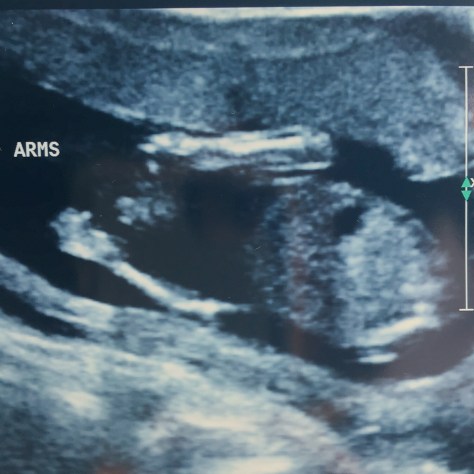

It’s when I pull out the next size of baby clothes and recall the times her older sisters wore them that I remember there was not suppose to be another bonus harney baby. Those clothes were suppose to be boxed up and headed off to good will. Actually truth be told, when we moved and bought our house there were a whole bunch of baby clothes that were suppose to be sorted through. Our move became a mad dash to the finish line which meant quite a few things that were stored in storage never got looked at before moving. It wasn’t until we started going through things during the winter months would we find out there was a baby bean growing inside.

Over this last year, Veil has easily woven herself into our family and no body felt displaced by her presence. I believe God knew what a busy family with 4 kids under 8 could handle when he began to knit her inside my womb. I ran out of time in my days during her pregnancy and realized it wasn’t until bedtime that I thought about her or did a kick count. I would worry and fear, “if I am just now thinking of her at 10 pm, what am I going to do when she is here?”. I knew I was already stretched to what seemed to be my limit.